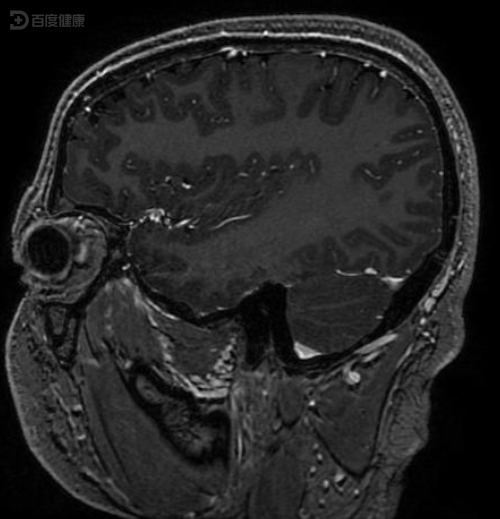

多形性黄色星形细胞瘤一例报道

结果:1,间变型星形细胞瘤 2,脑膜瘤